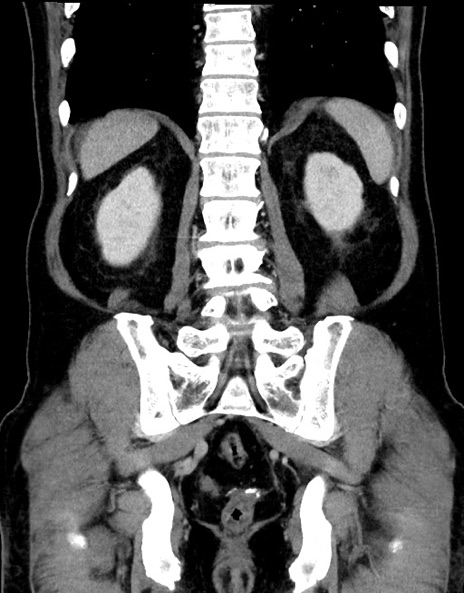

症例15(冠状断像)

【症例】70歳代男性

【主訴】腹痛

【現病歴】今朝から腹痛あり。全体的に痛い。特に左上の方。排ガスが今日はない。冷や汗が出る。

【既往歴】直腸癌術後

【身体所見】左側腹部〜上腹部に圧痛あり。腹膜刺激症状明らかなではない。軽度反跳痛。左下腹部に術後瘢痕あり。

【データ】WBC 7700、CRP 0.02